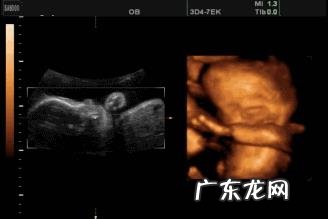

大家好!我叫豪豪,我呆在娘胎里5个月啦,大家是不是迫不及待地想知道我现在长什么样子呢?

这个时候都我可可爱啦,17周的时候我身高还是13㎝,但到了20周我有17㎝了,是不是长得很快呢 。

至于体重嘛,月初跟葡萄柚重量差不多,到月末我就有280g了,我妈妈带我去检查时,医生叔叔还说我争气呢,妈妈听了眉笑眼开 。

我的脸蛋越来越明朗了,看起来也俊了,不像以前那样软巴巴的,骨骼硬朗起来了呢,肌肉也比较发达了 。